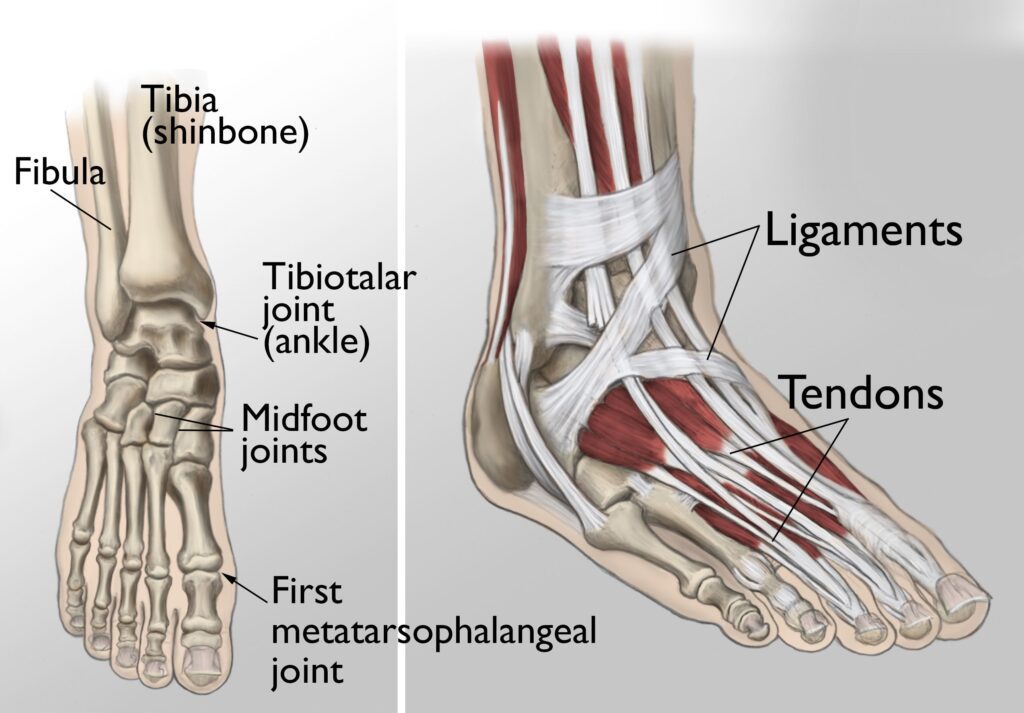

Treatment of Ankle / Heel / Foot Pain

Low Level Laser Therapy (LLLT), also known as Photobiomodulation Therapy (PBMT), is a highly effective, non-invasive, and drug-free treatment for various ankle heel and foot soft tissue injuries. Led by Dr Shikha Parmar, a GP with expertise in managing and resolving chronic musculoskeletal pain utilising LLLT as part of a holistic management plan. LLLT involves the application of red and near-infrared light to promote cellular repair in injured tissues. LLLT is safe and painless, and targets the root cause of the injury, unlike pain medications that simply mask the symptoms. Supported by scientific research from respected institutions such as Harvard University and NASA, LLLT is an evidence-based therapy for soft tissue injuries, including tendon and ligament injuries, bursitis, plantar fasciitis, nerve injury, osteoarthrits and stress fractures.